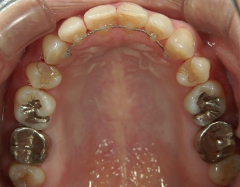

矯正歯科(全顎ワイヤー矯正)治療後

矯正歯科 治療後